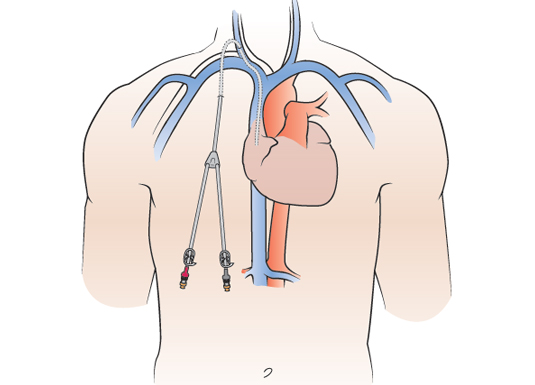

Patients who have renal failure need dialysis - a process by which the kidney function is done by a machine outside the body. For this blood has to be removed out and after filtering it has to be sent back into the body. Commonly this is done by creation of a fistula between an artery to a superficial vein in the arm. It takes approximately 6 weeks to be ready for dialysis use. Till then a double lumen catheter is placed in the neck. This can be used immediately after placement. The catheter could be non tunneled or tunneled. The non tunneled catheters are seen protruding out in the neck and are often associated with complications like infection and block. The tunneled catheters are known to be better with lesser short and long term complications. These tunneled catheters are inserted by Interventional Radiologists. Shown below are few cases of tunneled catheters.